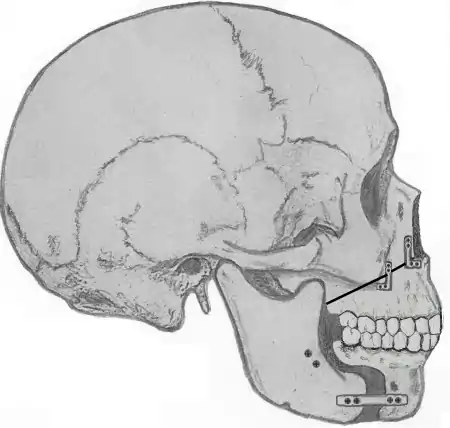

Genioglossus advancement

Genioglossus advancement (GA) also known as genial tubercle advancement (GTA), is a procedure that pulls the base of the tongue forward, usually to increase airway size due to deformity or a sleep breathing disorder. This procedure is frequently performed with either uvulopalatopharyngoplasty or maxillomandibular advancement surgeries.

Tongue muscles (genioglossus, geniohyoid and others) are attached to the lower jaw below the teeth. During a genioglossus advancement procedure, the surgeon cuts a small window or bone cut in the front part of the lower jaw (mandible) at the level of the geniotubercle where the genioglossus muscle attaches. This piece of bone, along with the attachment for the tongue (genial tubercle) is pulled forward and subsequently secured to the lower jaw, usually with a single screw or with a plate and screws.

This procedure is often combined with other surgeries such as uvulopalatopharyngoplasties or maxillomandibular advancement surgeries. It is rare to have this procedure performed as the only surgical treatment for sleep apnea, as obstruction in sleep apnea is most often at multiple levels (nose, palate, tongue, etc.).